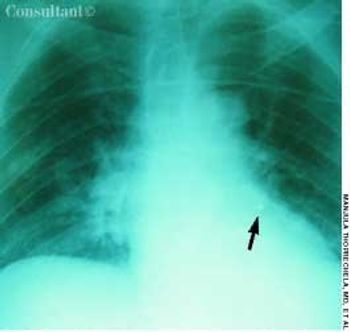

A 52-year-old woman was admitted tothe hospital with progressive shortnessof breath of 2 days’ duration. Bronchialasthma had been diagnosed 6 monthsearlier; inhaled corticosteroids, bronchodilators,and leukotriene antagonistswere prescribed. Despite aggressivetreatment, the patient’s dyspneaand wheezing worsened.